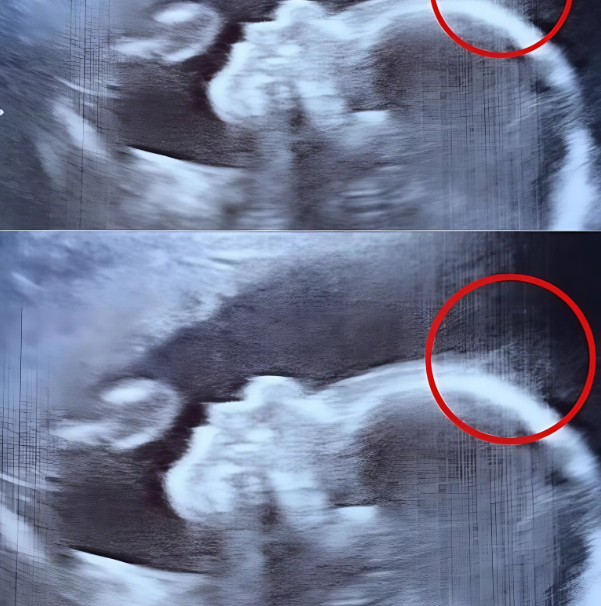

Lorsque Natasha Gent, une Britannique de 28 ans, s’est rendue à sa routine d’échographie à 20 semaines de grossesse, rien ne laissait présager que ce moment banal deviendrait inoubliable. Ni elle ni les médecins n’étaient préparés à ce qu’ils allaient découvrir sur l’écran.

C’est l’exclamation qui a résonné dans la salle lorsque le technicien, en déplaçant doucement la sonde, a repéré une silhouette floue — une forme inattendue qui ressemblait à… une chevelure.

Tout le personnel médical a d’abord pris cela à la légère, plaisantant sur le fait que le bébé de Natasha naîtrait probablement avec plus de cheveux que la moyenne. Mais ce qui attendait les parents à la naissance a dépassé toutes leurs attentes.